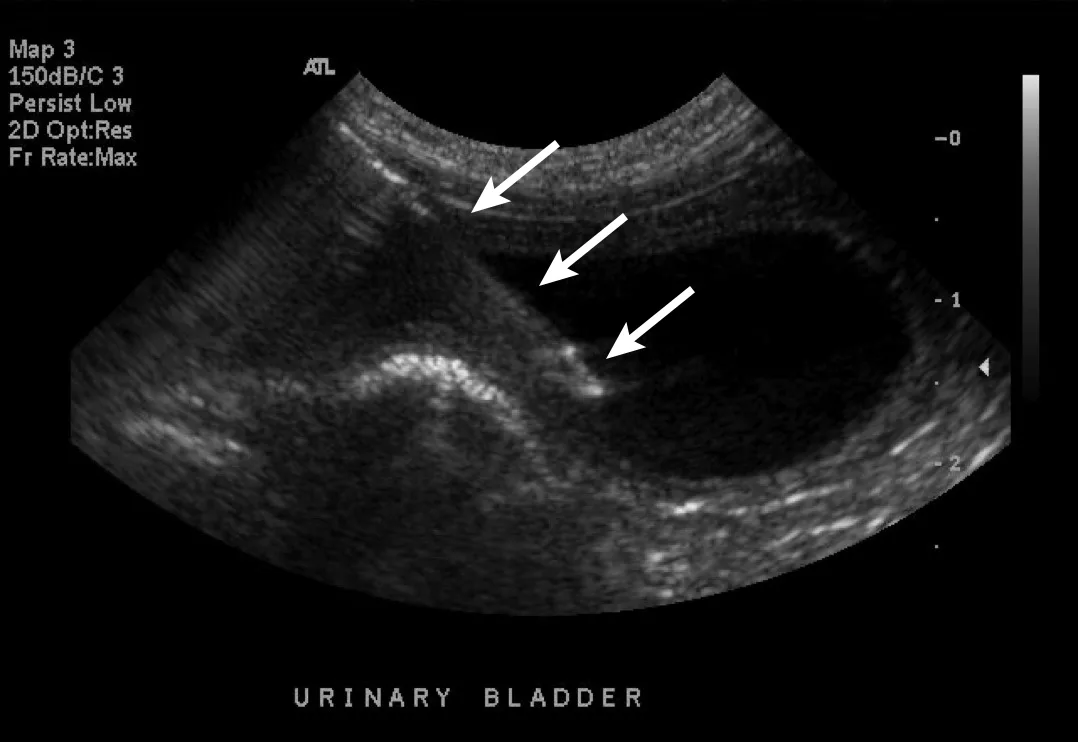

Urinary calculi are hyperechoic to the urine and can cast a distal acoustic shadow (ie, black streak under each calculus), regardless of the composition. In the author’s experience, increased power of the ultrasonography beam and advanced ultrasonography technology designed to minimize shadowing allow calculi to be at least 3 mm prior to creating a shadow. Lack of a distal acoustic shadow on small, gravity-dependent, hyperechoic foci does not therefore exclude diagnosis of sandlike calculi, although urinary sediment can have a similar appearance and can settle with gravity. Spatial resolution (ie, ability to distinguish 2 adjacent objects with the same echogenicity) is poor with ultrasonography, and multiple small calculi can appear as a single large calculus (Figure 4). Agitating the urinary bladder or repositioning the patient into sternal or lateral recumbency can help shift the calculi to determine the approximate length. In addition, measurements should be made parallel to the ultrasound beam for optimal accuracy; however, distal acoustic shadowing precludes these measurements. A reliable method of determining calculi type on ultrasound is not known.

Sagittal image of the urinary bladder with a collection of hyperechoic calculi (arrows) along the gravity-dependent dorsal border. Individual calculi cannot be seen due to poor spatial resolution. Echoic floating sediment, a nonspecific finding more common with higher-resolution probes, is present. Left, cranial; bottom, dorsal